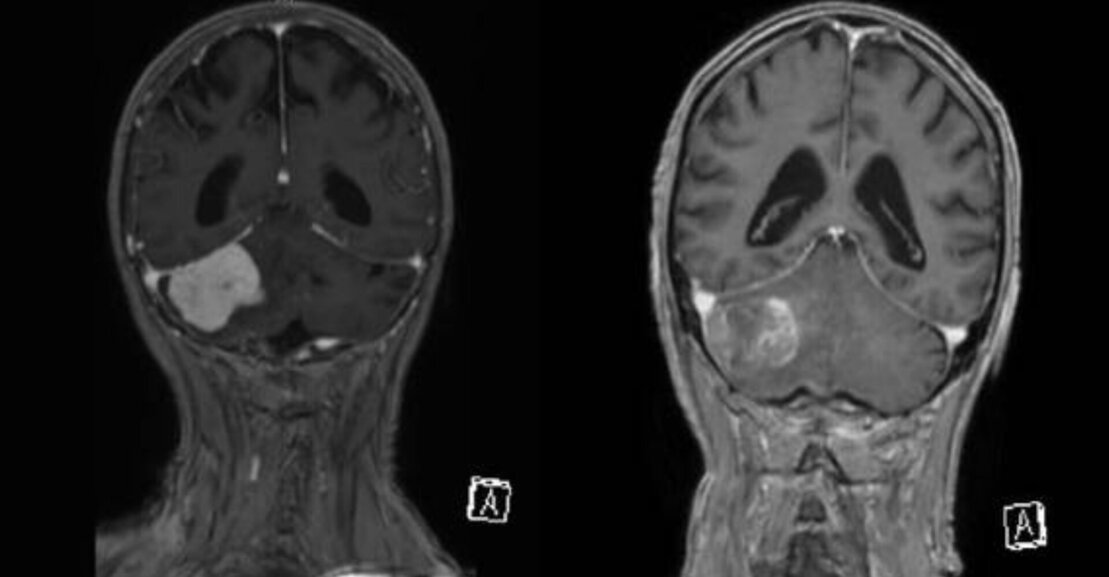

Für eine präzise Diagnose sind die neurologische Untersuchung und die Bildgebung (z. B. Kernspintomographie) wichtig. Diese Bilder können auch während der Operation zur Neuronavigation benutzt werden, um den Tumor und umliegende Hirnstrukturen genau lokalisieren zu können. Je nach genauer Lokalisation können auch weitere Untersuchungen nötig werden, wie z. B. audiometrische Untersuchungen bei Tumoren, die in der Nähe des Hörnervs (Nervus vestibulocochlearis) lokalisiert sind.

Das Medulloblastom ist der häufigste bösartige ZNS-Tumor bei Kindern. Typischerweise entwickelt er sich in der hinteren Schädelgrube – meist im IV. Ventrikel – und wächst sowohl schnell als auch infiltrierend gegen das Kleinhirngewebe. Sogenannte Abtropfmetastasen entlang der Hirnwasserwege (Liquorräume) sind möglich. Die Behandlung besteht in der möglichst kompletten chirurgischen Entfernung, gefolgt von einer adjuvanten Therapie bestehend aus Chemotherapie und bei Kindern ab ca. 4 Jahren zusätzlich Strahlentherapie. Die Behandlungsergebnisse zeigen in den letzten Jahren eine deutliche Verbesserung. Durch die beschriebene Kombinationstherapie werden heute 5-Jahresüberlebenswahrscheinlichkeiten von 70-80 % erreicht.